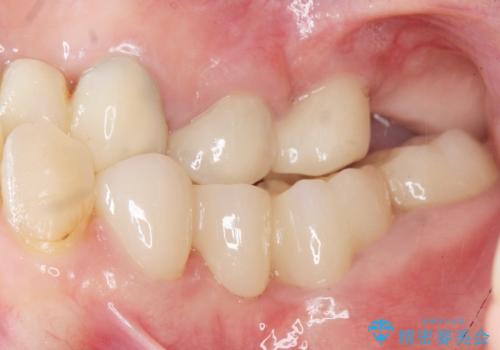

被せ物の種類:オールセラミッククラウン ベレッツァ

ご希望通り歯を抜かずに残すことができ、喜んで頂けました。

セルフメンテナンスしやすいよう、ブリッジと歯ぐきの間に歯間ブラシを通すことができるように作製しています。